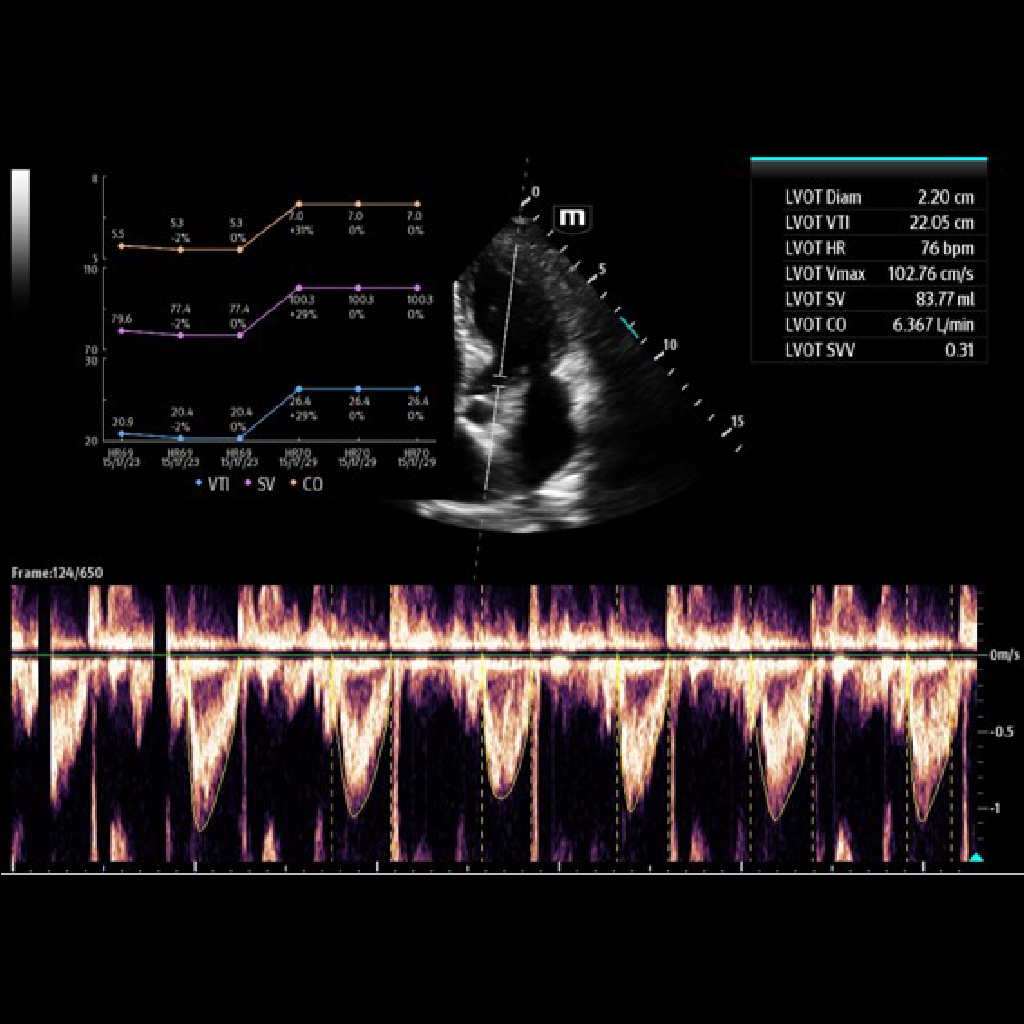

Aвтоматично измерва интеграла на скоростта и времето (VTI), ударния обем (SV), сърдечния дебит (CO) и вариацията на ударния обем (SVV) в сърцето.